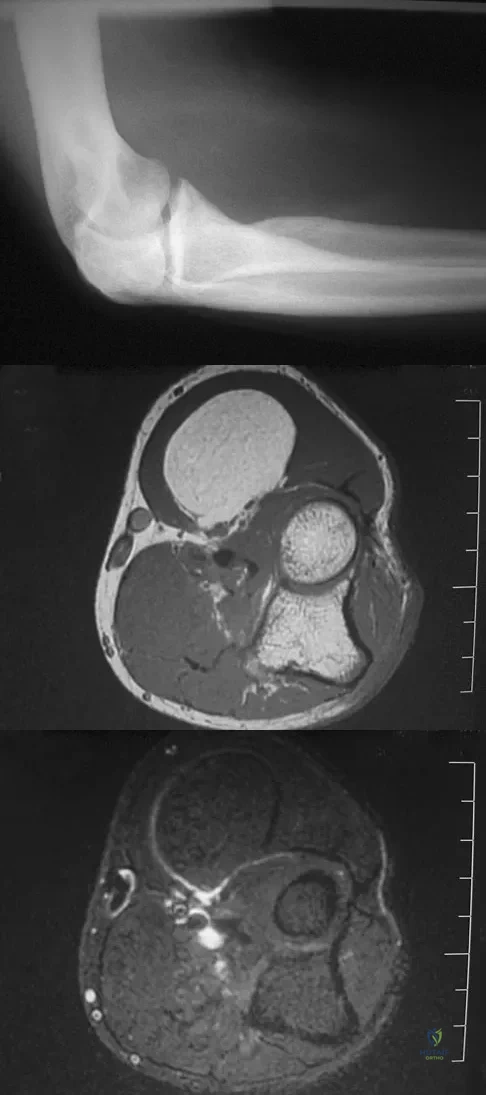

A 65-year-old woman has had chronic aching discomfort involving her elbow for the past 6 months. Radiographs and a biopsy specimen are shown in Figures 38a through 38c. What is the most likely diagnosis?